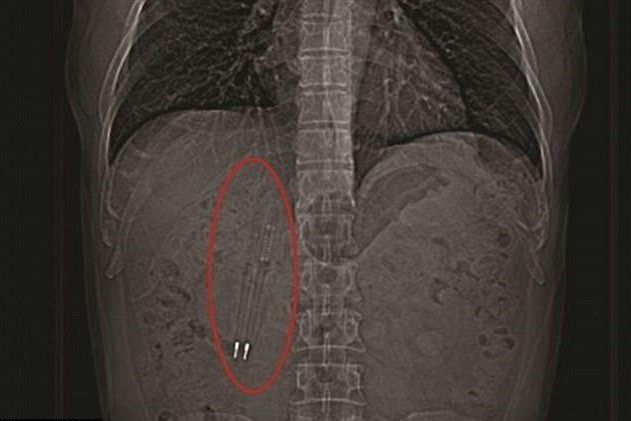

▲男子體內的兩支筆,筆尖和彈簧都很清晰可見。(圖/翻攝自微博)

王先生表示,事後曾想過要去醫院拿出來,但時間一久,身體也沒有其他異狀,就忘記自己體內住著兩隻筆的事情,過了36年才鼓起勇氣到醫院檢查,在電腦斷層掃瞄中還可以清楚看到筆的金屬彈簧和筆尖。昆山中醫院消化科的徐主任說,這兩支長約12公分的筆從口中被吞下後,經過了食道、胃、幽門最後抵達十二指腸,因為筆的長度就跟十二指腸差不多,所以無法在往下掉。

醫生研究後決定用內窺鏡將筆從食道拿出來,手術非常順利,只花了大約30分鐘,徐主任表示,幸好有趕快做手術,因為發現有一支筆刺破了腸壁,已經化膿。王先生回憶,當初吞下的筆應該是紅色塑膠外殼,拿出來的時候已經完全變成黑色的,但裡面的筆芯還完好無缺。